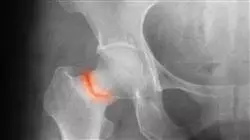

I traumi alla pelvi e agli arti inferiori rappresentano sfide significative nel campo della medicina d'urgenza. Come professionista sanitario, è essenziale possedere conoscenze specialistiche nella gestione e nel trattamento di queste lesioni per fornire cure di qualità ai pazienti che ne soffrono. Presso TECH Università Tecnologica, ti offriamo l'opportunità di diventare un esperto in Traumatologia d’Urgenza del Bacino e degli Arti Inferiori attraverso il nostro Esperto Universitario. In questo programma acquisirai una profonda conoscenza delle emergenze traumatiche che colpiscono il bacino e gli arti inferiori. Imparerai come eseguire una corretta valutazione clinica e radiologica, nonché come interpretare i risultati per stabilire una diagnosi accurata. Esplorerai anche le strategie di trattamento più aggiornate, comprese le tecniche chirurgiche, la gestione conservativa e la riabilitazione, con l'obiettivo di ottenere il miglior recupero e la migliore funzionalità per i pazienti.